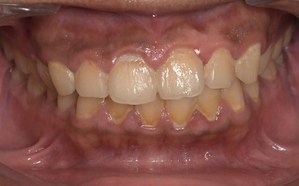

症例2

Before

症例

after

歯周病検査(治療前)

歯周病検査(治療後)

レントゲン写真

基本情報

年齢・性別 41歳・男性

主訴 主訴:歯ぐきから出血する

治療部位:全顎

治療内容 1.歯周ポケット検査、資料取り(レントゲン写真14枚・口腔内写真)、歯磨き指導

2.歯磨き指導チェック、縁上の歯石除去

3.縁下の歯石除去4回

4.再評価(歯周ポケット検査・レントゲン写真14枚・口腔内写真)

5.メインテナンス

治療期間 1日

治療費 合計:14,160円

内訳(全て保険診療3割負担)

・初診検査、歯磨き指導、縁上の歯石除去:3,630円

・レントゲン写真、縁下の歯石除去①:3,040円

・縁下の歯石除去②:1,530円

・歯磨き指導チェック、縁下の歯石除去③:2,070円

・縁下の歯石除去④:1,530円

・再評価:2,360円

(2022年5月現在現在)

リスク・副作用 ・歯石除去後すぐは歯ぐきを触っているため歯ぐきに違和感や痛みを感じる場合がある

・歯石除去により今まで腫れていた歯ぐきが引き締まり歯ぐきが下がる可能性がある

・歯ぐきが引き締まって下がることにより歯面が今までより露出し知覚過敏の症状がでる可能性がある

・歯石除去後、歯磨きを怠ると細菌が歯周ポケットのより深部まで入ってしまうため歯周病が悪化してしまう可能性がある

・一度歯周病になると再発しやすい為、定期的なメインテナンスが必要になります

治療方針 1.歯磨き指導

2.歯ぐき上の歯石除去

3.歯ぐき下の歯石除去

4.再評価

5.定期的なメインテナンス

特記事項 ・着色除去(PMTC)は自費治療のため希望しませんでした。

・右下7番の歯周ポケット5mmは親知らずの関係もあり、このまま維持していくことを説明しています。

・他4mmの歯周ポケットに関しては歯垢が少し残っていた為、再度歯磨き指導と、縁下の歯石を確認して様子をみることにしました。

担当者所見 全体的に出血が見られたのと、奥の歯ぐきは炎症があり歯周ポケットが深かった為、まずは歯ブラシの当て方+歯間ブラシ3Sサイズを使用して頂き炎症を落ち着かせました。

両方毎日使用して頂いた為、スムーズに歯周病治療を行うことができました。毎日のホームケアが不十分だと、なかなか結果に繋がらず、治療期間も長くかかってしまう為、患者様の協力が歯周病治療を成功させるためにはかなり重要になっていきます。

そして一度病気になった歯ぐきは再発しやすい為、今後は3ヶ月に1度の定期的なメインテナンスで、この状態を維持できるよう一緒に管理していきます。